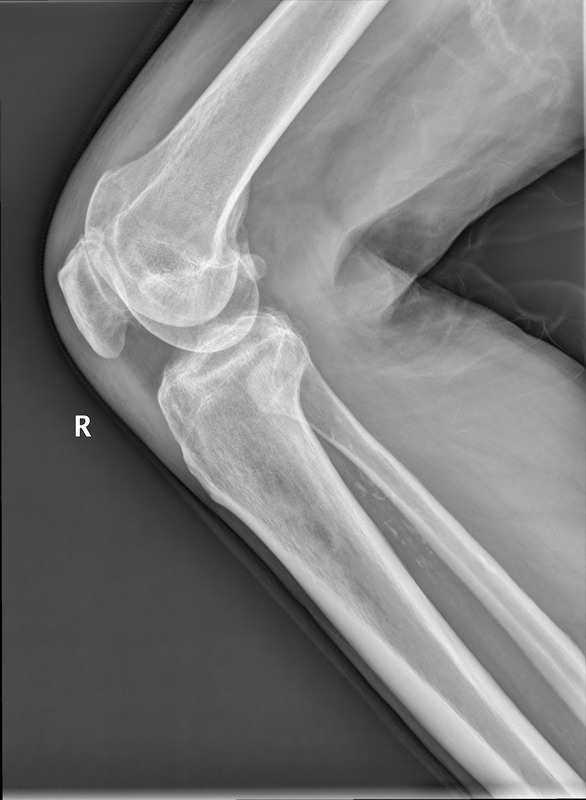

以下是引用随光逐影在2010-4-12 8:14:00的发言:[br]1)双膝关节退行性改变。2)双小腿软组织内钙化(骨间膜钙化?血管壁钙化?)。